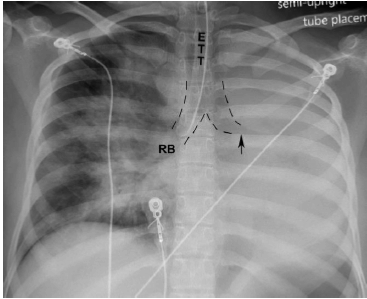

Qual o diagnóstico da radiografia de tórax ilustrada abaixo?